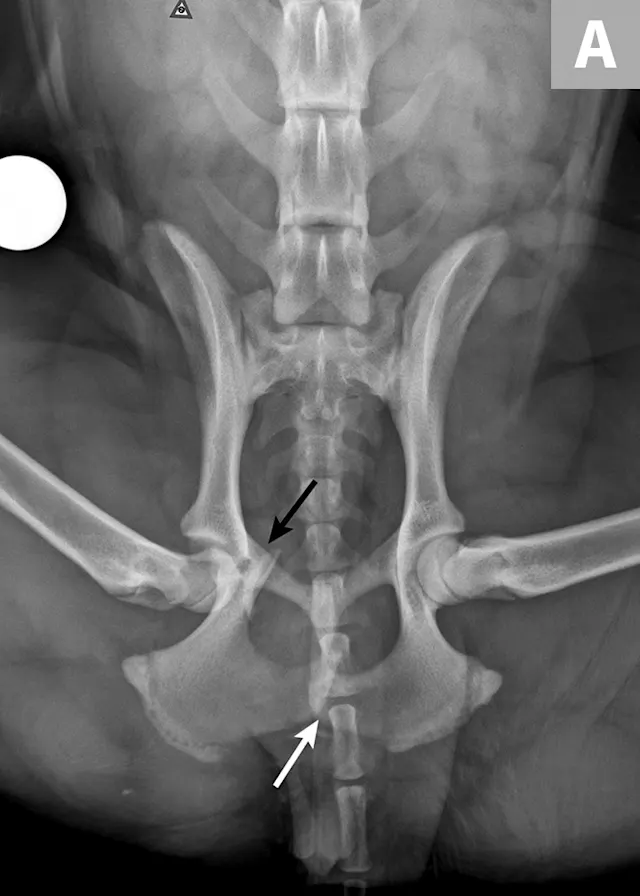

There are many different types of pelvic fracture configurations, and nearly half of pelvic injuries in dogs and cats involve fractures of the ilium.3,4,7,8 Clinically significant fractures involve the weight-bearing axis of the pelvis that includes the ilium and acetabulum (Figures 1-3). Although not a fracture, sacroiliac luxation is potentially significant because the sacroiliac joint is a component of the weight-bearing axis of the pelvis. Unilateral or bilateral fractures or luxations may occur, and it is common for patients to have a combination of pelvic injuries.3,4,7,13

FIGURE 1A

An 11-year-old intact female Welsh corgi with injuries of the weight-bearing axis of the pelvis. Ventrodorsal (A) and lateral (B) projection images show a left sacroiliac luxation with cranial and ventral displacement (black arrow). Pubic fracture with lateral displacement (dashed arrow) and an oblique tibial fracture (white arrows) were additional comorbidities. The tibial fracture was treated surgically with an internal plate fixation, and the pelvic injuries were managed conservatively.